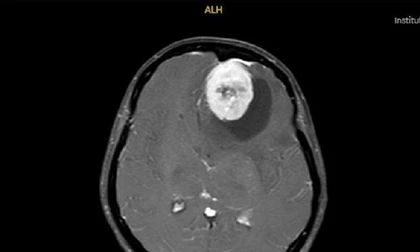

Cứu bệnh nhân bị khối u khủng kéo sụp tai xuống cổ

Sức khỏe

TPO - Mang trong mình khối u sợi thần kinh bẩm sinh hiếm gặp từ khi chào đời, nam thanh niên 24 tuổi ở Vĩnh Long phải sống chung với tình trạng biến dạng nghiêm trọng vùng mặt, tai và cổ. Các bác sĩ Bệnh viện Chợ Rẫy đã thực hiện ca phẫu thuật phức tạp, bóc tách khối u nặng gần 1kg, giúp người bệnh cải thiện sức khỏe và diện mạo.